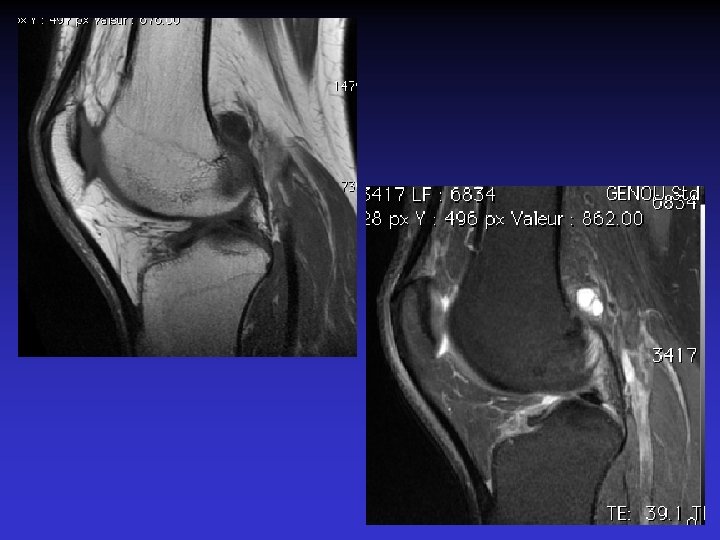

DIAGNOSTIC DIFFERENTIEL • Rupture du LCA • Tumeur synoviale

RUPTURE DU LCA

SVN